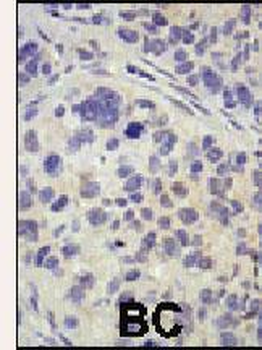

Formalin-fixed and paraffin-embedded human cancer tissue reacted with the primary antibody, which was peroxidase-conjugated to the secondary antibody, followed by DAB staining. This data demonstrates the use of this antibody for immunohistochemistry; clinical relevance has not been evaluated. BC = breast carcinoma; HC = hepatocarcinoma.